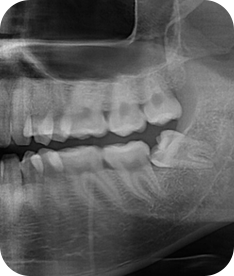

치주치료 전후사진

B

A